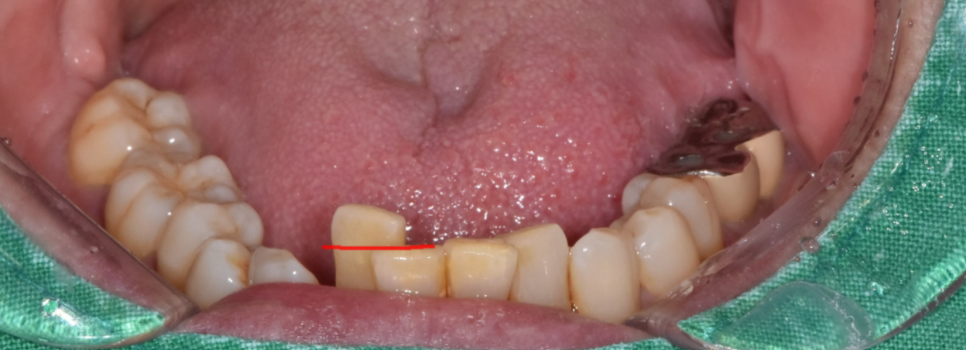

사진을 보시면 아래 앞니 1개가 솟구쳐 올라와있죠?

다른 치아에 비해 키가 유독 큰 모습입니다.

아래 앞니 흔들림이 심한 경우

(주로 손으로 밀어도 움직임이 강할 경우)

발치가 요구됩니다.

지금 상태에서는 뼈가 치아를 붙잡아줄 힘이 없고,

이 환자분도 결국 발치 후 임플란트를 권유드렸습니다.

240622

240517 붙어있는 치석들